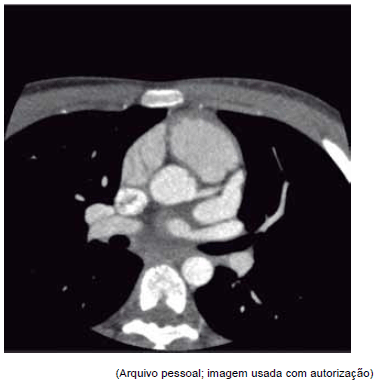

Este corte tomográfico pode ser compatível com qual diagnóstico?